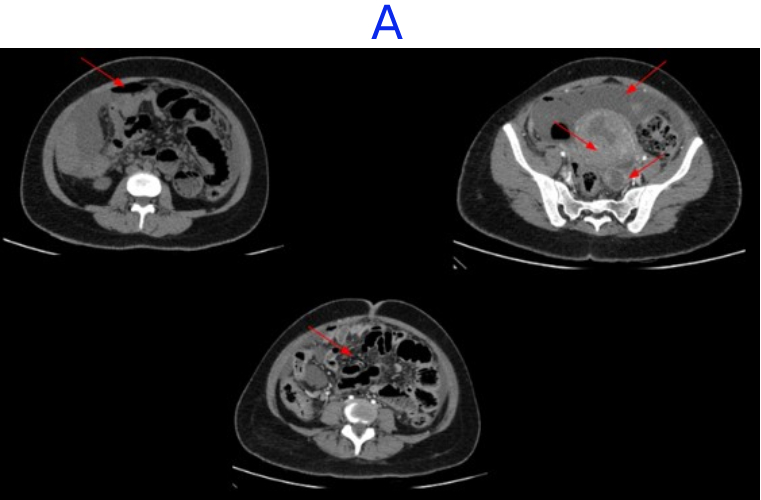

CECT ABDOMEN AND PELVIS - DAY 1

• A. Mild pneumoperitoneum. Few heterogeneously enhancing fibroids seen. Tubular hypodense area in left adnexa - likely pyosalpinx Diffuse greater omental fat stranding and peritoneal thickening - suggestive of peritonitis.

• B. Tubular hypodense area in left adnexa - likely pyosalpinx. Subserosal fibroid in upper corpus.Few loculated fluid pockets with air foci are seen in the pouch of douglas